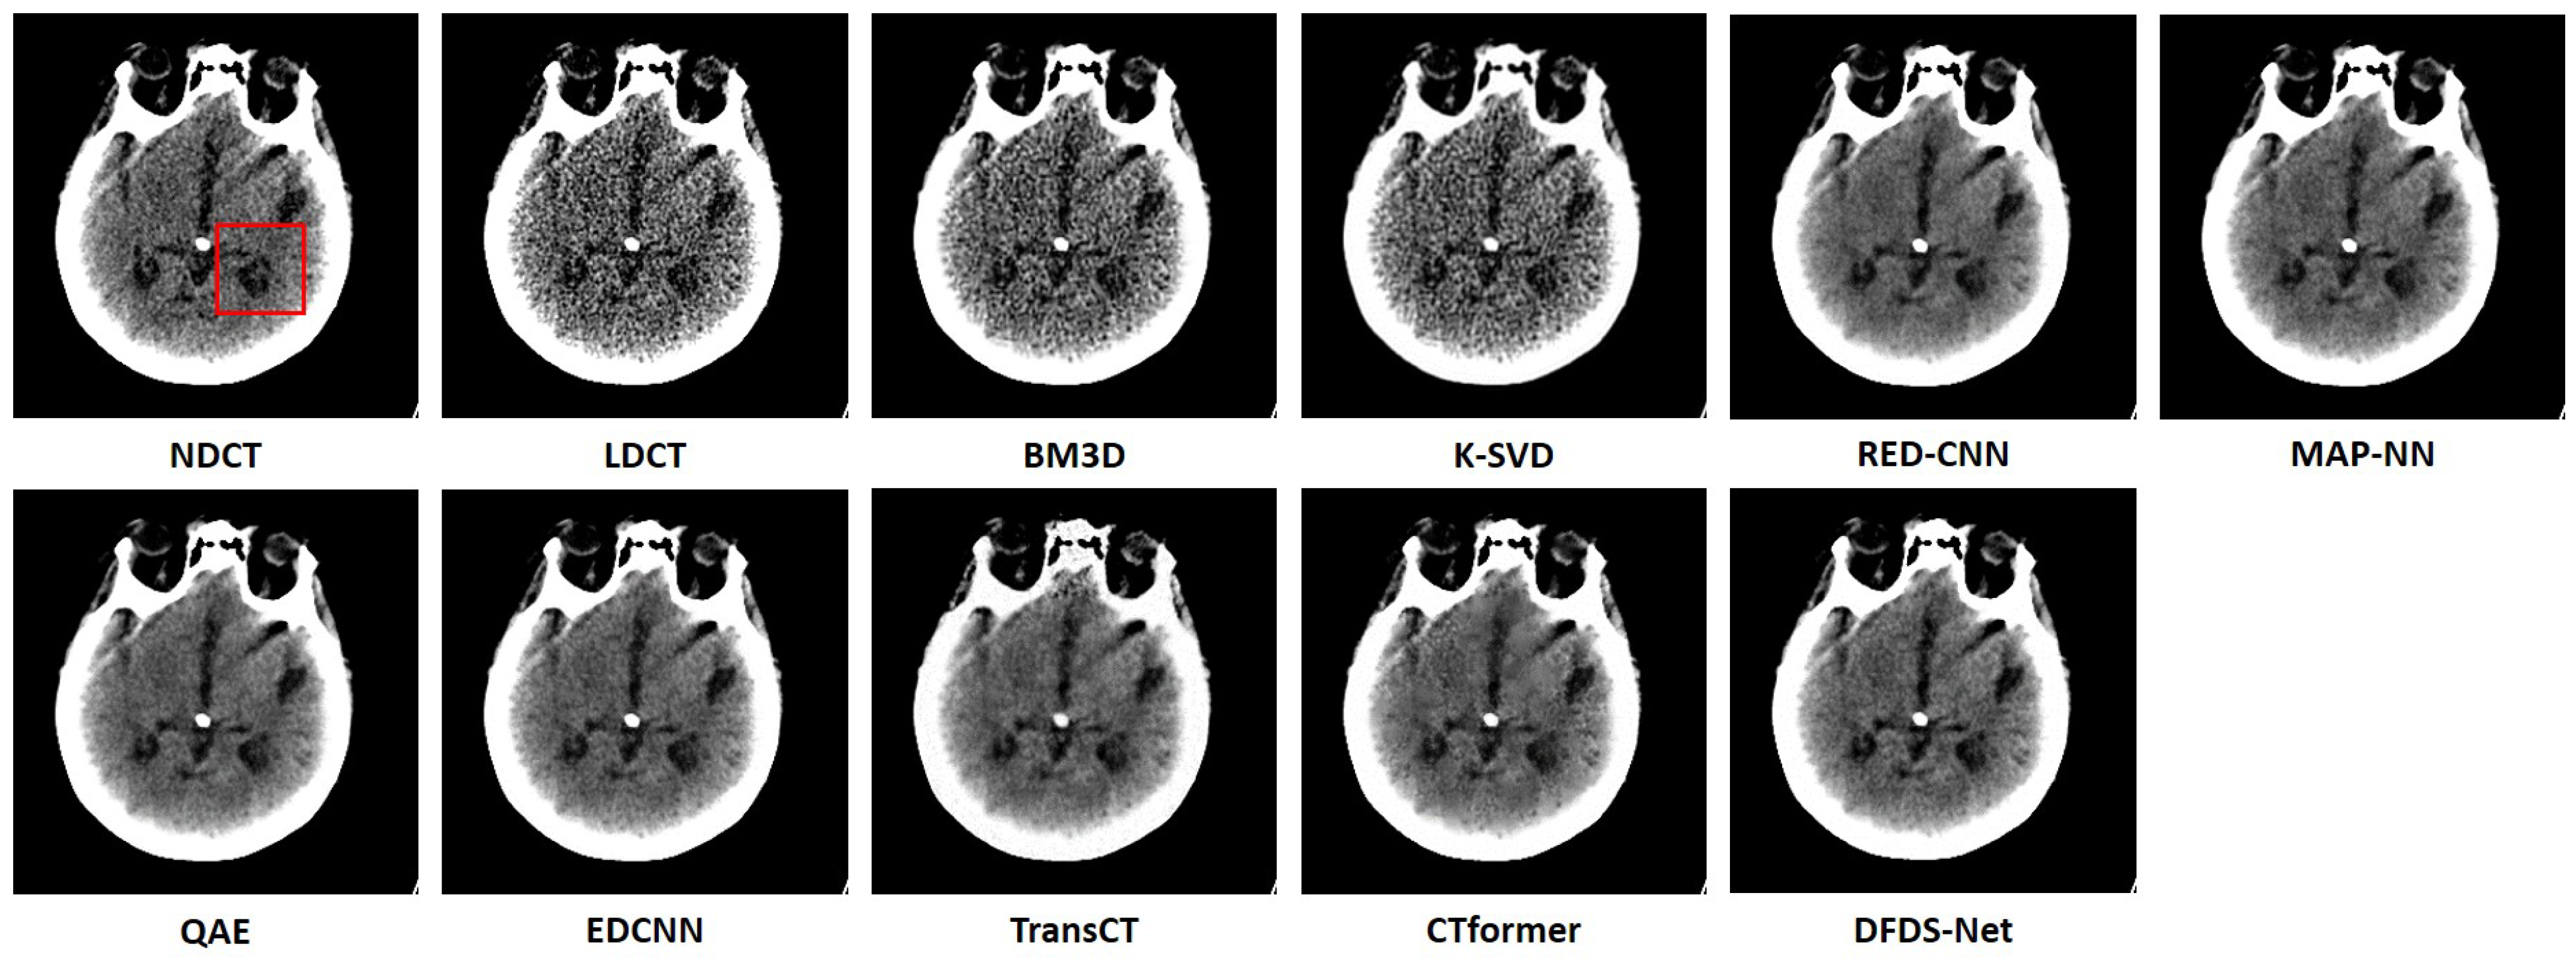

Noise reduction performance: The left section of Table 6 presents the experimental results on the head CT dataset. We observe that the proposed method was superior to all compared methods, with the SSIM and PSNR achieving the highest value and the RMSE the lowest. Figure 5 visualizes the noise reduction effects across different models on this dataset. Notably, BM3D and K-SVD, unlike other compared methods which successfully reduced noise, were less effective in noise reduction, resulting in images still marred by significant noise. In contrast, images denoised by TransCT and CTformer exhibited only slight noise. RED-CNN and EDCNN, while effective in noise reduction, tended to over-smooth the boundaries of distinct soft tissues, thus diminishing clinical diagnostic value. Other comparative methods like MAP-NN and QAE showed similar denoising performance. However, WaveletDFDS-Net stood out for its superior restoration of details, offering a higher quality and fidelity. As shown in Figure 6, the zoomed images over a region of interest have clearer contrasts in the details. The evaluation metrics for the images presented in Figure 5 are detailed in the left section of Table 7.

Figure 5. Comparison of the qualitative performance of WaveletDFDS-Net and other well-known low-dose CT denoising methods on the head dataset. The display window is [0, 80] HU.

Figure 6. The zoomed images over the region of interest (ROI) marked by the red box in Figure 5. (a) BM3D, (b) K-SVD, (c) RED-CNN, (d) MAP-NN, (e) QAE, (f) EDCNN, (g) TransCT, (h) CTformer, (i) WaveletDFDS-Net.